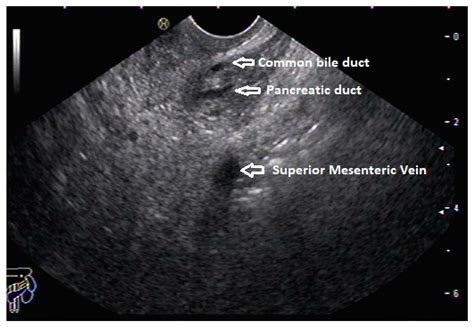

• Imaging Tests: Such as ultrasound, CT scan, or MRI to visualize the pancreas and its ducts.

Diagnosing an enlarged pancreatic duct involves a combination of medical history, physical examination, and diagnostic tests. Common diagnostic procedures include:

These diagnostic tools help healthcare providers determine the cause of the enlarged pancreatic duct and develop an appropriate treatment plan.